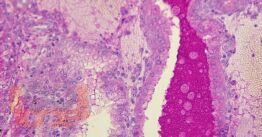

Монография посвящена анализу влияния урогенитальной инфекции на морфологию и функционирование плаценты у женщин с бессимптомным течением микоплазменной, уреаплазменной и хламидийной инфекций. Представлены современные данные о гистологическом строении компонентов маточно-плацентарной области – эндометрия, базальной децидуальной оболочки, ворсинчатого хориона. Освещена проблема формирования плацентарной недостаточности на фоне урогенитального инфицирования. Изложены результаты морфологического исследования плацент при разных видах урогенитального инфицирования.